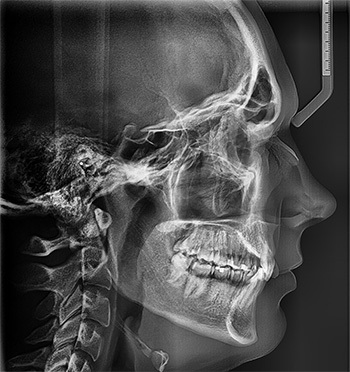

The patient, a 23-year-old member of the National Guard, wanted to get started with his treatment; however, he was scheduled for deployment from South Carolina to Arizona. After discussing his unique situation during the initial consultation (Figs. 1–4), we determined we could achieve the treatment goals with clear aligner treatment along with remote monitoring. This report details his successful results managed with minimal office visits.

Fig. 1

Initial records revealed:

• Class I malocclusion with posterior crossbite on the left

• Severe overbite

• Moderate overjet

• Moderate upper crowding

• Severe lower crowding

• Thin attached gingiva #27